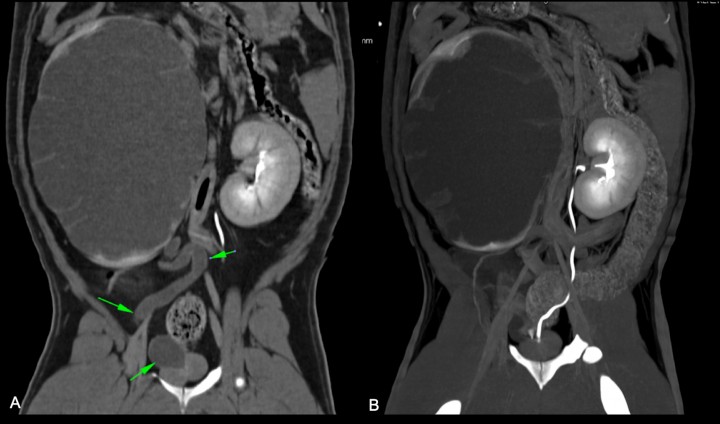

Como planificación quirúrgica, se realiza con el paciente en decúbito esternal una tomografía computarizada abdominal pre y postcontraste endovenoso (120 KVp, 150 mA 1 s/rotación, pitch 0,9, espesor de corte 1,25 y 2,5 mm con filtros de hueso y tejido blando, respectivamente). El estudio tomográfico revela una distensión grave del riñón derecho con un fino resto cortical que presenta realce postcontraste. El uréter derecho se encuentra distendido moderadamente con un recorrido tortuoso hasta su desembocadura en la uretra prostática (Fig. 4A). El riñón izquierdo presenta una arquitectura normal, pero su uréter desemboca también en la uretra prostática (Fig. 4B), lo cual aporta una información relevante no observada en la ecografía. No se evidencian otras alteraciones en las estructuras incluidas en el estudio.

<p>Imágenes tomográficas. (<strong>A</strong>) Corte dorsal del trayecto tortuoso del uréter derecho sin contraste (flechas verdes). (<strong>B</strong>) Corte dorsal del trayecto y desembocadura en la uretra prostática del uréter izquierdo.</p>

Imágenes tomográficas. (A) Corte dorsal del trayecto tortuoso del uréter derecho sin contraste (flechas verdes). (B) Corte dorsal del trayecto y desembocadura en la uretra prostática del uréter izquierdo.

En el caso descrito, la radiografía simple permitió evidenciar inicialmente una masa retroperitoneal y la ecografía confirmó la presencia de hidronefrosis con hidrouréter derecho, secundaria a ectopia ureteral del mismo. Sin embargo, fue la TC con urografía la que permitió el diagnóstico definitivo de ectopia ureteral bilateral con hidronefrosis e hidrouréter derecho secundario.